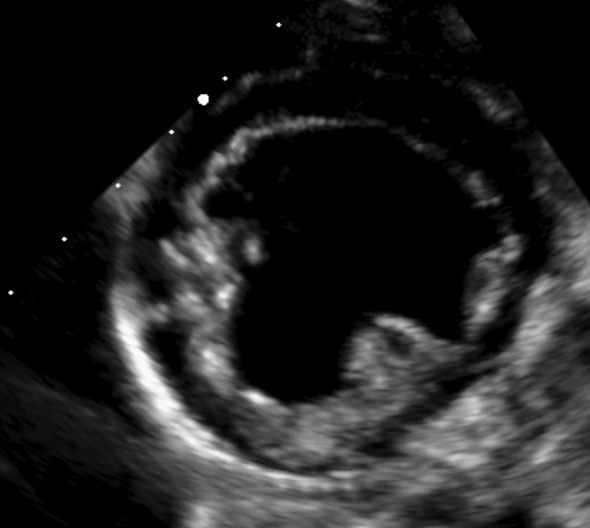

Analyse de cas cliniques illustrés par des images fixes et/ou des vidéos d’échocardiographie (2D, TM, Doppler).

Objectif : apprendre à repérer, décrire et interpréter les anomalies échographiques dans une démarche diagnostique rigoureuse, jusqu’à l’établissement de diagnostics différentiels.